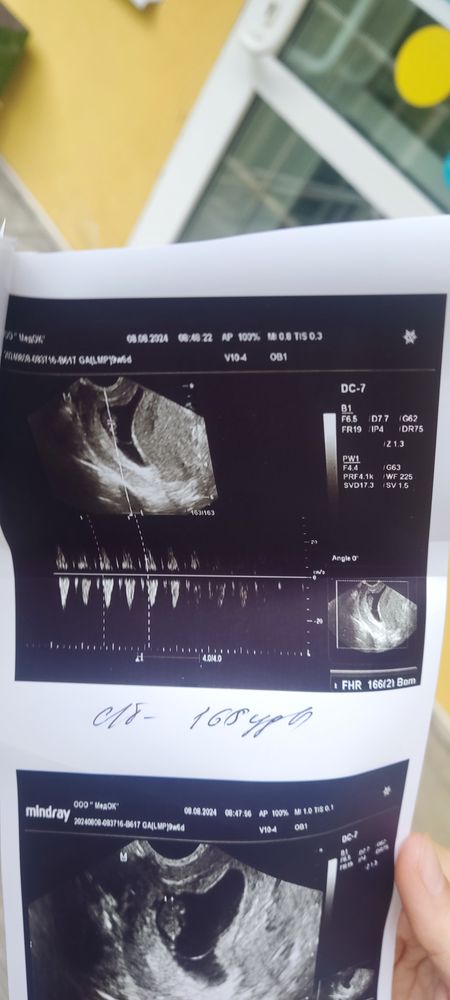

Подскажите про УЗИ

Все норм в узи, тонус отдыхать больше ❤️

Нормальное УЗИ ,тонус бывает у многих на таком сроке.Побольше отдыхайте и не поднимайте тяжести.

Вообще у вас тонус, я бы к врачу сходила, тонус на маленьком сроке опасен